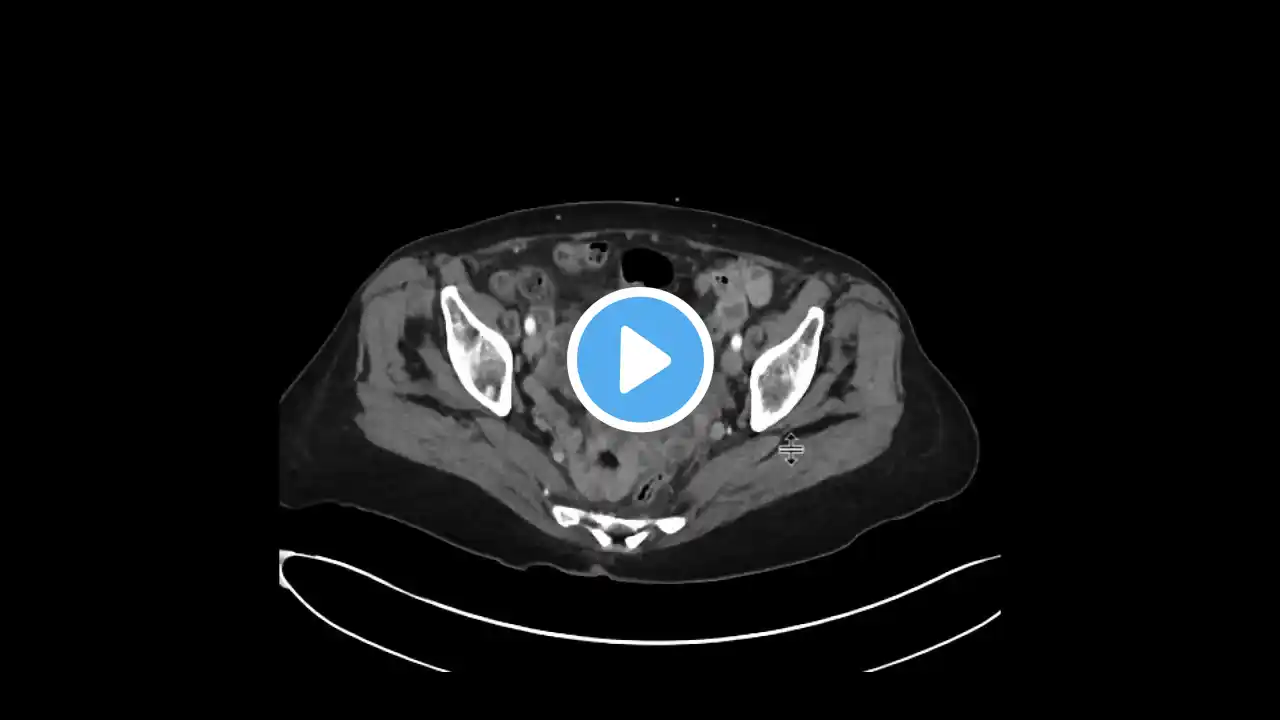

Dr Elizabeth Plimack highlights the types of tests used in the detection of bladder cancer. Michael Molnar explains which procedures were performed by his urologist to determine whether he had cancer. View more at http://curetoday.com/ CURE: Combining science and humanity to make cancer understandable.